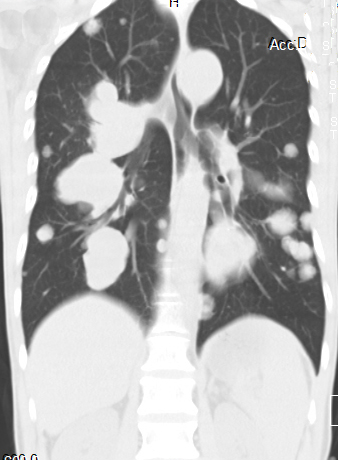

[影像描述]

双肺多发转移灶,大小不等,呈棉花团样

CT表现为粟粒、单发、多发大小不等结节,呈圆形或椭圆形,密度均匀、轮廓清楚,肺野为著。

1、肺内单发或多发球型结节影,大小不一,边缘光滑,密度均匀,多分布于肺外围

3、两肺布满粟粒样结节

4、肺纹理呈网状改变或沿淋巴管呈细小结节状改变,HRCT表现为小叶间隔增厚,沿肺纹理有细小结节影,同一患者出现多种形态转移征象.